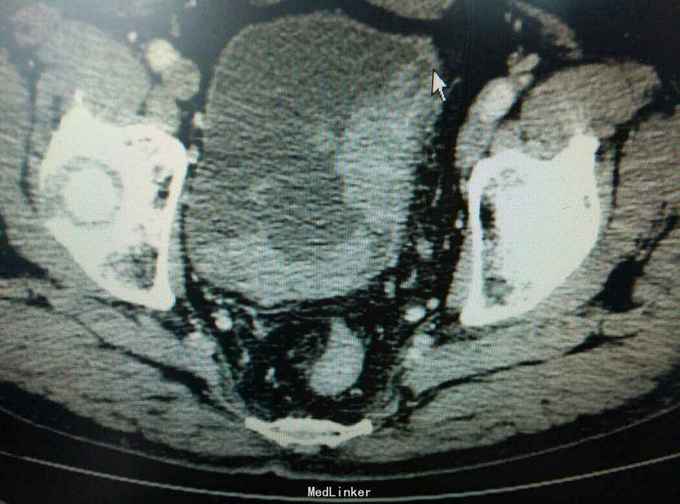

患者三年前无明显诱因下出现无痛性肉眼血尿,单位体检发现膀胱肿瘤,因心里恐惧,未就诊,三年期间患者阅读了日本作者近藤诚的著作不要再上肿瘤的当等书籍,拒绝治疗,希望与肿瘤共存,三年间反复血尿,最后是血红蛋白剩40g时候发生缺血性心脏病时候住院,反复劝导后同意治疗,活检报告浸润性尿路上皮癌,患者拒绝全膀胱,接受电切治疗。

行膀胱肿瘤电切术,术后常规灌注吡柔比星30mg,术后三月时再次行诊断性膀胱肿瘤电切术,术中未见复发,至今已九个月未见复发